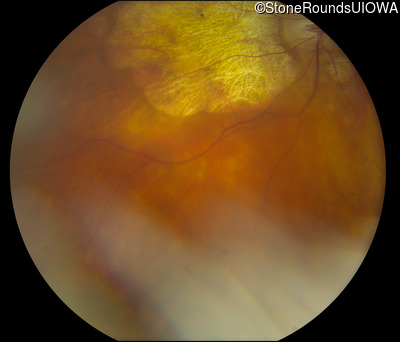

Fundus Photography - Right - 20/400 sc

Exemplar